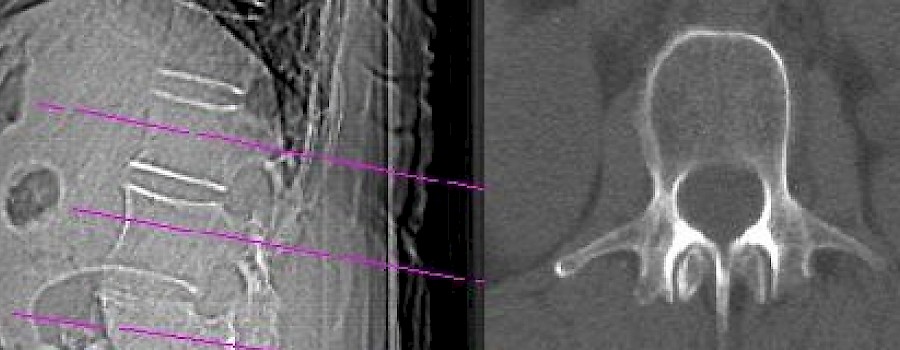

Als Knochendichtemessung, auch Osteodensitometrie oder DPX (engl. dual photon X-Ray), werden medizinisch-technische Verfahren bezeichnet, die zur Bestimmung der Dichte, bzw. des Kalksalzgehaltes des Knochens dienen.